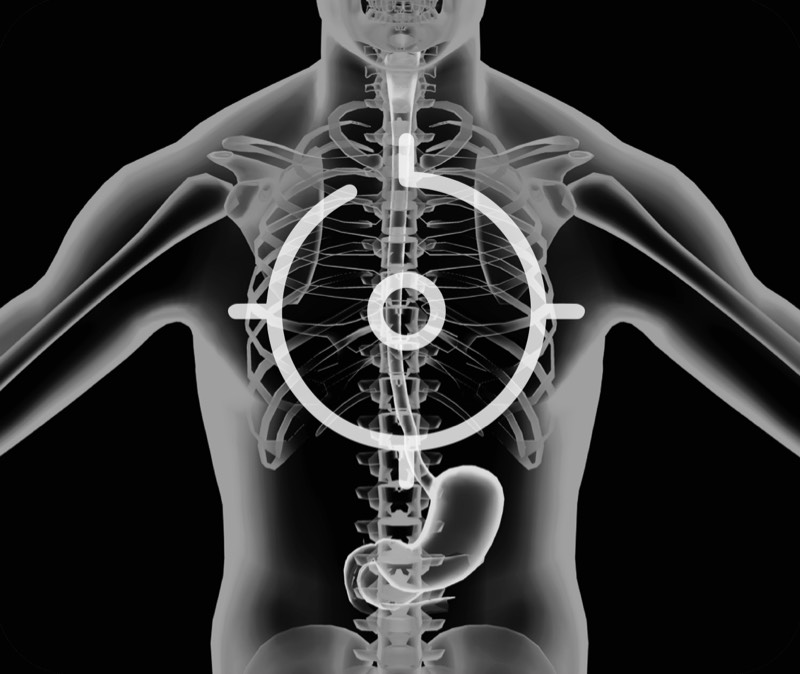

360°电子环形扫查与高清内镜影像相结合,提供了良好的插入性能和高清的内镜图像

卓越的宽频设计,满足医生探查不同深度的组织和器官

搭配独立超声主机,为临床提供更优质的超声画质